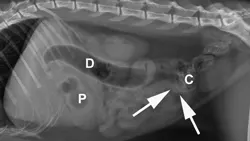

Abdominal radiography: Left/right lateral and VD views.

Radiographic Findings: The stomach (St) and duodenum (D) are severely distended with fluid and gas, suggesting intestinal obstruction or possibly pancreatitis with secondary ileus.

There is a 1.5-cm rounded opaque structure (arrows) in the caudal abdomen, to the left of the descending colon on the VD view. It is partially obscured by feces in the colon (C) on the left lateral view. The remaining organs and serosal detail appear normal.

Comments: We often perform left and right lateral radiographic views of the abdomen in cases of suspected GI foreign bodies and obstructions since the fluid and gas disperse into different portions of the GI tract. For example, any gas in the stomach rises to the pylorus (P) in left lateral recumbency and may outline a foreign body anchored to this region; this is particularly useful in suspected linear foreign bodies, which typically anchor to the tongue or pylorus and subsequently plicate varying degrees of small intestine.